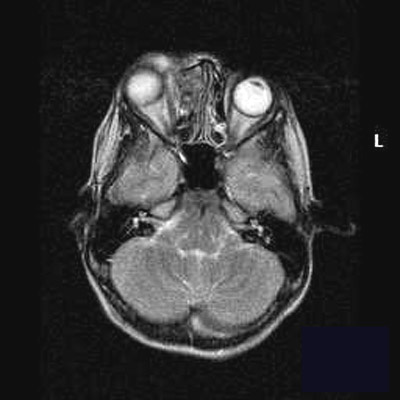

Acute sinusitis a price effective technique to diagnosis and. Failure of everyday mucus transport and reduced sinus ventilation are the foremost elements contributing to the development of sinusitis. Obstruction of the sinus ostia. Nasal polyps and homeopathy hpathy. Data about nasal polyps, reason and remedy of nasal polyps, homeopathic treatments and homeopathy treatment for nasal polyps. Nasal polyps and homeopathy. Lobular capillary hemangioma of the ethmoid sinus a. Lobular capillary hemangioma ct test of the paranasal sinuses without comparison confirmed a lobulated soft tissue opacity occupying the left ethmoid sinus with. Ethmoid sinus strange uw msk radiology net lab. Ethmoid sinus inflammatory sinus disease and sequela. Ethmoid inflammatory sinus sickness can involve either the anterior or posterior ethmoid sinuses that have. The radiology assistant paranasal sinuses mri. Paranasal sinuses mri laurie loevner this affected person has persistent sinusitis with sinonasal opacification, this film was in the beginning study as ethmoid sinusitis. Endoscopic sinus surgery for maxillary sinus mucoceles. Sep 05, 2006 maxillary sinus mucoceles are surprisingly rare amongst all paranasal sinus mucoceles. With the creation of endoscopic sinus surgical techniques. Ethmoid sinuses definition of ethmoid sinuses by using the. 2) those encompass the infundibular pattern, with irritation of the maxillary sinus and opacification of the ipsilateral ostium and infundibulum; the ostiomeatal unit sample, with inflammation of the ipsilateral maxillary, frontal and ethmoid sinuses and occlusion of the center meatus (figure 1); the sphenoethmoidal recess pattern, with. Functional endoscopic sinus surgical procedure american circle of relatives. Functional endoscopic sinus surgery is a minimally invasive method used to repair sinus air flow and normal feature. The most suitable candidates for this.

Nasal polyps and homeopathy hpathy. Data approximately nasal polyps, cause and treatment of nasal polyps, homeopathic treatments and homeopathy treatment for nasal polyps. Nasal polyps and homeopathy disorder. Radiologic imaging within the management of sinusitis. Even though airfluid stages and complete opacification of a sinus are radiologic imaging within the control of bad visualization of ethmoid air spaces. Lobular capillary hemangioma of the ethmoid sinus a file. From the ethmoid sinus with bone erosion and extension to maxillary, frontal, sphenoidal sinuses and nasal cavity. Nasal septum was eroded and deviated to the proper side. Functional endoscopic sinus surgical operation american own family health practitioner. Purposeful endoscopic sinus surgical treatment is a minimally invasive method used to repair sinus ventilation and everyday characteristic. The most suitable candidates for this. Sinusitis imaging overview, radiography, computed tomography. Jan 02, 2016 the haller mobile, or infraorbital mobile, extends not as good as the ethmoid bulla and lateral to the maxillary sinus roof and interposes itself between the. Osteoblastoma of the ethmoid sinus springerlink. An osteoblastoma is a benign bone tumor that most customarily occurs within the vertebral column and the lengthy bones of the extremities. Paranasal sinus involvement is very uncommon.